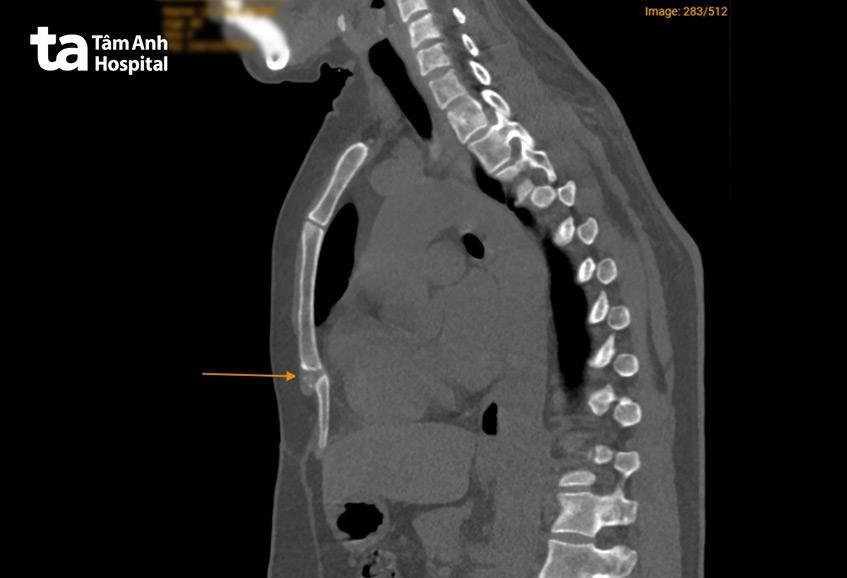

Tỷ lệ mắc bệnh không được ghi nhận rõ, đa số các chuyên gia đều ghi nhận đây là loại tổn thương hiếm gặp. Về tiêu chuẩn chẩn đoán ở ca này, ngoài triệu chứng đau trực tiếp ở mũi ức khi thăm khám, hình ảnh phim chụp CT cho thấy mỏm mũi kiếm kéo dài (> 6 cm), khớp giữa thân và mũi kiếm xương ức bị vôi hóa và có khối sụn lớn (kích thước 3 x 2 x 1.5 cm). Chính khối sụn này đẩy mũi ức quặp vào phía sau gây đau.